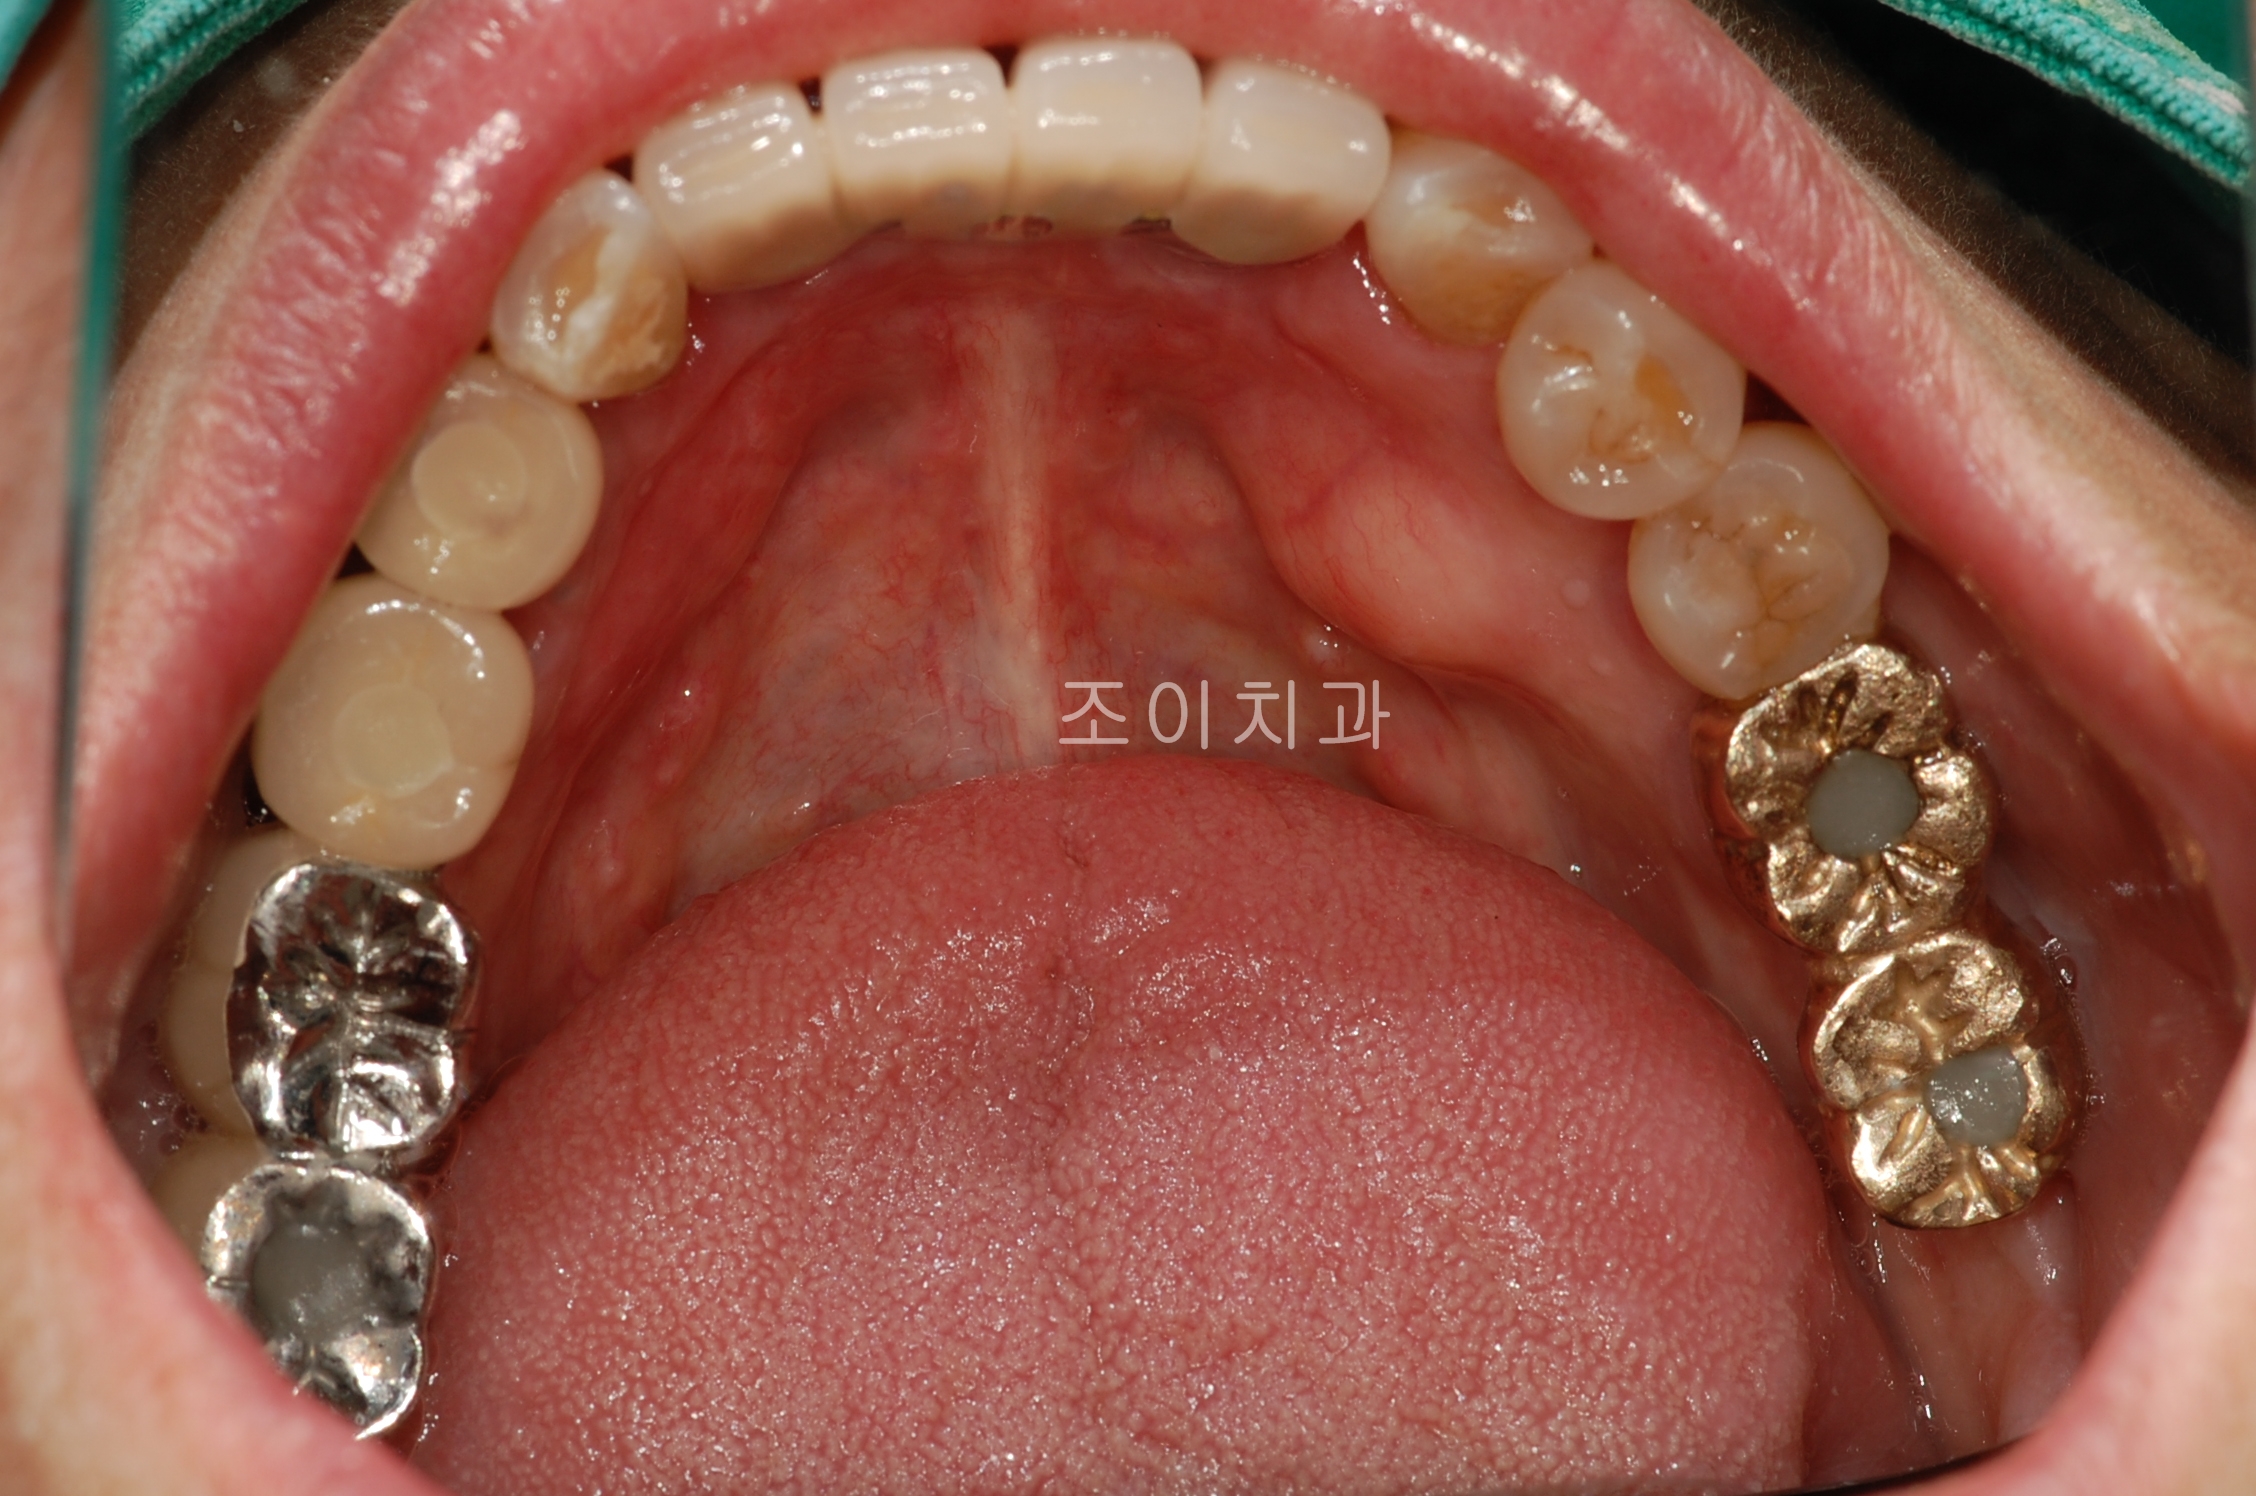

임플란트 보철. 조이치과에서는 임플란트 시술 후 관리를 위하여 보철물 위에 스크류홀을 형성하는 SCRP보철을 주로 이용합니다.

SCRP를 만들기 위해서는 정확한 임플란트가 정확한 위치와 경사로 심겨져야합니다.